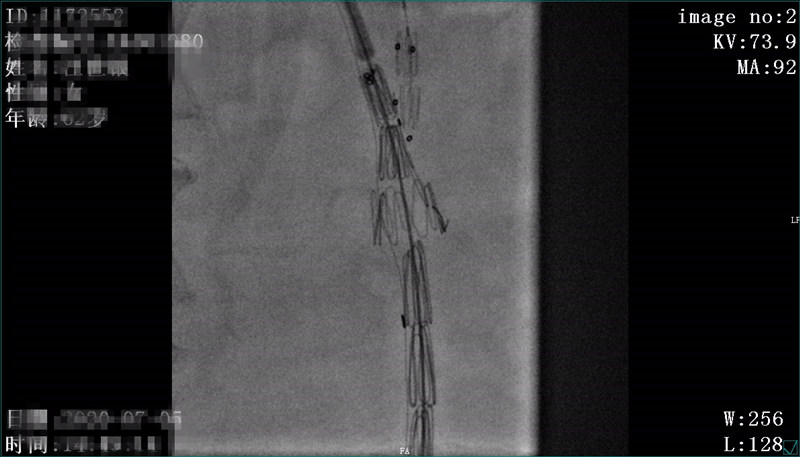

术中开窗后定位

术后造影,主动脉弓处破口消失,左颈总动脉显示可,左锁骨下动脉显示良好,胸主动脉显示良好,原扩张段消失,支架周围未见明显内漏。